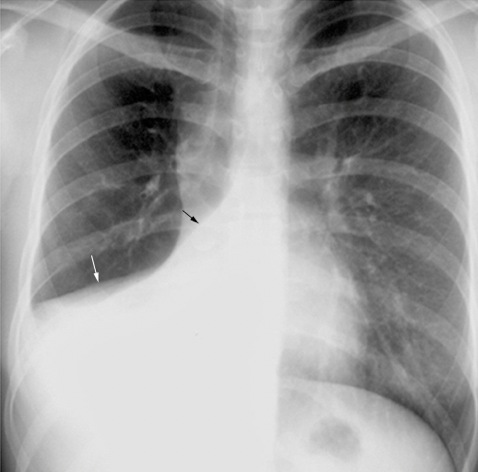

what is an example of a condition in which the heart borders are blurred?

A

-pulmonary oedema

-check the ratio of the heart size: width of thorax (normal adult ratio is less than 50%)

-if heart is enlarged, it may indicate cardiomegaly, but you cannot judge this accurately on AP film

-check borders - edges of the heart should be clear which ensures nothing is obscuring this silhouette eg pulmonary oedema